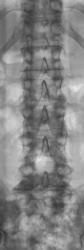

Физиологический лордоз уплощен, возможно, за счет дискогенной боли. Сколиоза нет, хотя при одностороннем корешковом синдроме, вызванном протрузией диска, сколиоз (в сторону выпадения диска) как правило бывает, т.е. можно предположить наличие центральной (медианной) грыжи диска, которая в равной степени оказывает компремирующее воздействие как на правый так и на левый корешки. Антелистез L3. Узлы Шморля в телах L3-S1 - свидетельство перенесенной экстремальной осевой нагрузки - расположены типично - на одной линии один над другим. Высота межпозвонковых дисков L3-4, L4-5, L5-S1 снижена, там же субхондральный склероз замыкательных пластин и краевые костные разрастания - проявления остеохондроза указанных дисков. Симптом "задней распорки" в L4-5 - косвенный признак грыжи диска. Отсутствие дужки L5 или L4 (не могу утверждать однозначно т.к. на представленной боковой спондилограмме "срезаны" остистые отростки и имеет место люмбализация S1)- ВПР или последствия оперативного вмешательства по поводу грыжи L4-5, не хватает данных анамнеза.

В принципе, Валентин Львович, причина болей в пояснице и тазобедренных суставах понятна. Коллега Кузнецов все написал. Добавлю, т.к. в анамнезе отсутствуют оперативные вмешательства на позвоночнике имеет место аномалия развития поясничного отдела позвоночника в виде отсутствия дужки L5, спондилолиз и спондилолистез L3 и далее все выше указанные изменения.

Отсутствие дужки L5, спондилолиз L3? Не вижу

спондилолистез (или псевдоспондилолистез) да, спондилолиза, как и отсутствия дужки, не видно

Все дуги целые. Расстояние между остистыми L4 и L5 увеличено за счет локального кифоза в этом сегменте.